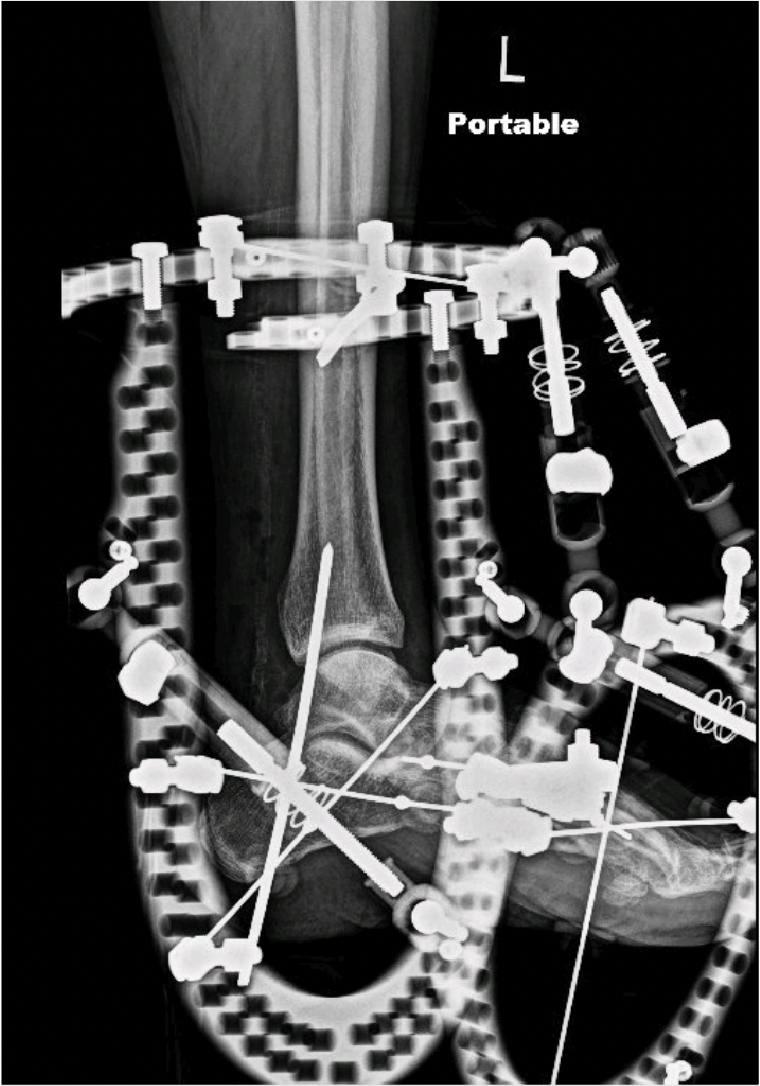

Plain radiographs of the foot revealed advancing destruction and diastasis across the tarsometatarsal joint complex and subluxation of the midtarsal complex. Given the complexity of the deformity in multiple planes and likely progression to an unbraceable foot, we offered the patient an acute correction. Stage 1 would be through a butted frame with hexapod configuration followed by consideration of intramedullary fixation as a second stage if necessary.

Apply the hexapod frame after restoring the calcaneus from equinus. We typically use skinny wires versus half pins, but this is up to surgeon preference. With all connecting struts loosened, manipulate the reducible foot deformity in all planes. This occasionally demands strategically placed small incisions to relieve bone or joint impediments with release using osteotomes and or elevators. When satisfied with the gross appearance of foot architecture, tighten the struts and obtain intraoperative images to confirm anatomic alignment.

It is now necessary to perform final reads of both acute and gradual strut alignment numbers. If these numbers remain consistent with preoperative planning, make no changes to the established deformity correction prescription. If identified changes result from acute corrections performed during the surgery, enter these numbers into the program and develop an updated prescription. Our experience has shown that acute correction mitigates significant postsurgical gradual deformity correction. Regardless, once achieving full correction, osseous consolidation is then permitted. Commonly, our patients remain in these frames for at least 6 weeks and up to 12 weeks. In this recovery time, we determine, based on clinical and radiographic findings, whether the patient will proceed to a staged internal fixation or move directly to extremity bracing.